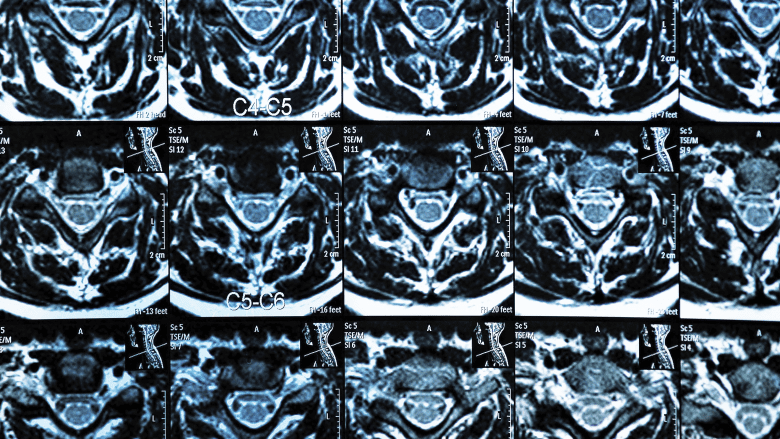

MRI scan of the cervical spine showing multiple spinal segments

Magnetic resonance imaging (MRI) is a powerful diagnostic tool used to evaluate spine pathology.

This scan provides detailed images of soft tissues, including discs, nerves, and the spinal cord, which are not visible on X-rays or CT scans.